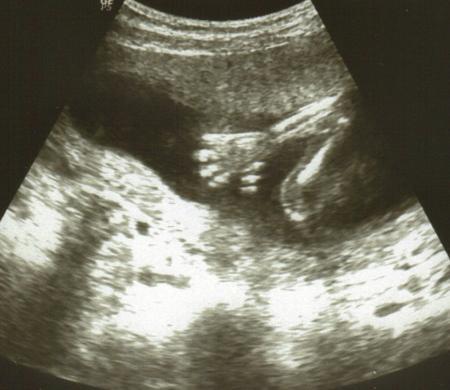

Ich hatte heute nach 6 langen Wochen wieder VU. Das Zwergle entwickelt sich total super, hat bei einigen Daten am US sogar teilweise bereits die 20.SSW ausgerechnet. Gewicht liegt in etwa bei 263 g, Größe zirka 18,2 cm. Kopfumfang ist auch bereits bei 14 cm, wird denke ich wieder ein großer Kopf werden (mein Sohn hatte KU 36). GMH ist total super bei 5,3 cm Länge, also alles in allem prima Werte. Als der Arzt fragte ob wir wissen wollen was es wird war ich ganz still und hab dann nur meinen Freund angesehn. Er dann nach ein paar Sekunden: 'Nein!' Also bleibt es weiterhin bei einer Überraschung Auch meine Blutwerte sind vollkommen in Ordnung. Hab dann heute auch die Zuweisungen fürs Organscreening und für einen Glukosetest bekommen. Wegen meinem Kreislauf solle ich nur zusehen dass ich mehr esse und trinke, was mir aber leider ein wenig schwer fällt. Bin heute bei 17+5 und nächster Termin beim FA ist erst wieder am 5.3. (7 Wochen warten)

Bild zu Auch zurück vom FA - Forum für Juni - Mamis

Gib mir die Hand!

Bild zu

Toll! Freut mich für dich dass alles so klasse ist. Soolche süßen Bilder, wahnsinn..dieser Arm und diese Hand.. Tolle Qualität! Und großen Respekt an dich..ich könnte das nie, es mir dann nicht sagen lassen..